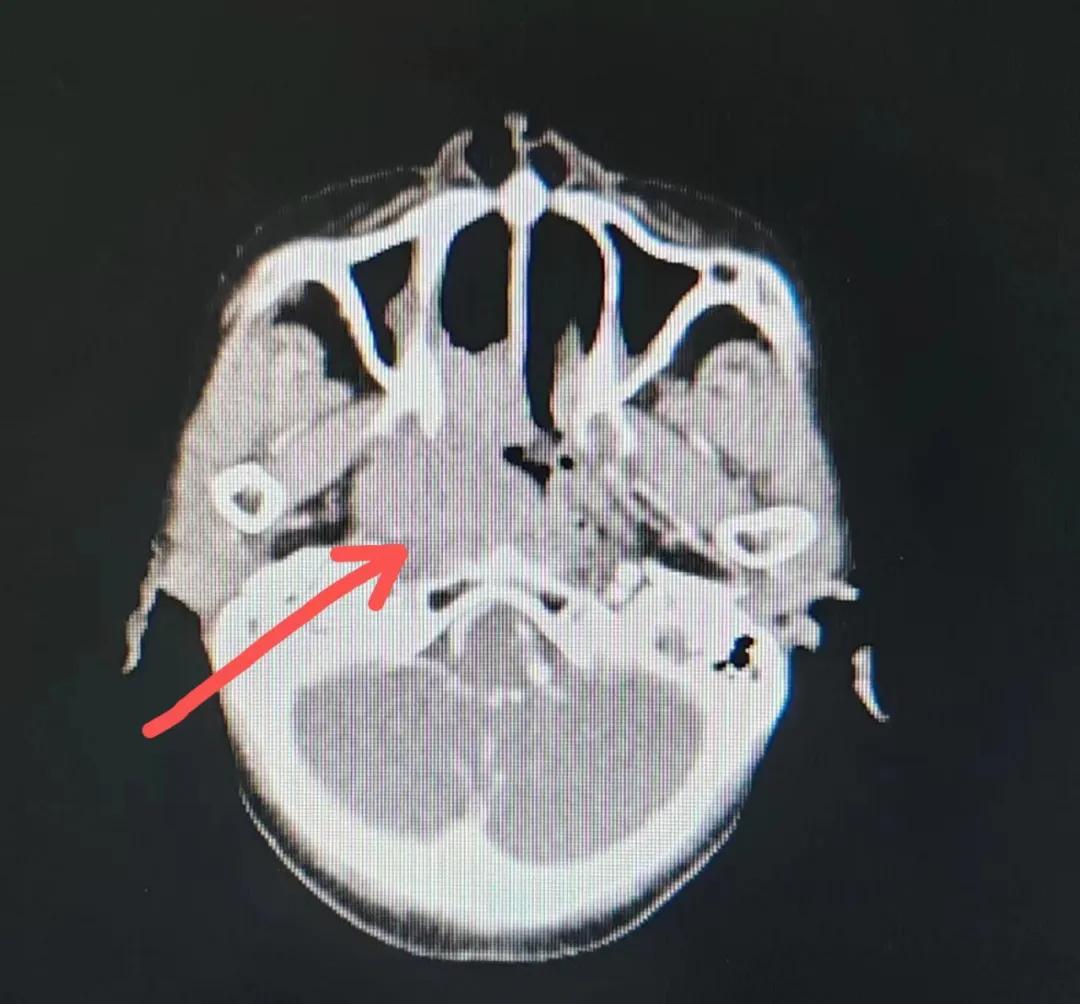

漯河市二院精準(zhǔn)放療救治七旬鼻腔惡性淋巴瘤老人

70歲的彭阿姨,5個(gè)月前因鼻部瘙癢伴流血不止在當(dāng)?shù)卦\所治療,瘙癢和出血癥狀不但沒(méi)有得到有效控制,反而進(jìn)行性加重,并出現(xiàn)鼻腔堵塞、進(jìn)食困難,經(jīng)外院病理活檢確診為“鼻腔惡性淋巴瘤”。不斷加重的病痛已嚴(yán)重影響了老人的生活質(zhì)量,為求診治,患者及家屬于今年2月份慕名來(lái)到了市二院放療科。

治療前

老人因鼻部腫物堵塞鼻腔并且侵犯鼻咽導(dǎo)致鼻塞、疼痛、吞咽困難,身心都備受煎熬,趙亮主任在詢問(wèn)其病史期間幾度落淚。趙亮主任向患者及家屬解釋說(shuō):“現(xiàn)代放療比過(guò)去的傳統(tǒng)放療設(shè)備先進(jìn),技術(shù)不斷提升,能對(duì)腫瘤區(qū)域的照射劑量進(jìn)行優(yōu)化,做到準(zhǔn)確定位、精準(zhǔn)照射,同時(shí),最大限度地降低正常組織的受量,對(duì)全身情況影響很小。”

考慮到患者年齡較大、體質(zhì)差,手術(shù)難度大,且常規(guī)的放射治療難以保護(hù)患者晶體造成患者雙眼視力損傷,放療團(tuán)隊(duì)以最快的速度制定了精準(zhǔn)放射治療方案并開(kāi)始為其實(shí)施治療。僅僅數(shù)日后,老人腫塊出血即得到控制,腫塊明顯縮小,放療20次后腫塊迅速縮小!

治療后

放療結(jié)束,除了放療處的皮膚輕微放射性皮炎外,基本沒(méi)有什么不良反應(yīng)。復(fù)查發(fā)現(xiàn),鼻腔淋巴瘤已不可見(jiàn),目前患者已康復(fù)出院。